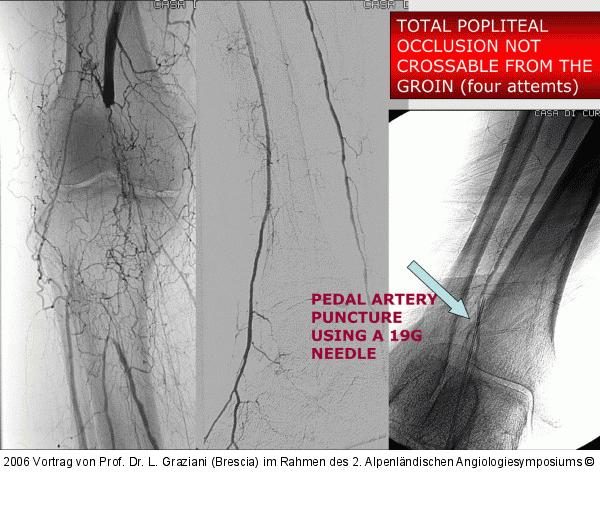

Vortrag von Prof. Dr. L. Graziani (Brescia) im Rahmen des 2. Alpenländischen Angiologiesymposiums

PTA of the foot arteries in diabetics: Extremities Extreme Angioplasty

Abbildung 65: P.O.B.A.